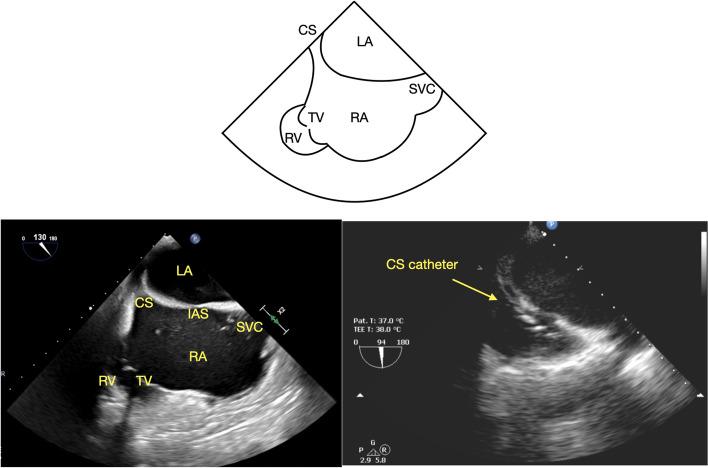

Transesophageal echocardiographic imaging plays an important role in assessing coronary sinus anatomy prior to placement of a retrograde cardioplegia cannula. The coronary sinus can be imaged in the long axis by advancing the TEE probe from the mid-esophageal 4-chamber view or using a modified mid-esophageal bicaval view, while a short axis view can be obtained in the mid-esophageal 2-chamber view. While use of a transgastric view is only briefly mentioned in the literature as an alternative to mid-esophageal views, the authors commonly include it in our comprehensive transesophageal echocardiographic exam of the coronary sinus. This study examines the various imaging strategies. We hypothesize that the transgastric view offers comparable coronary sinus imaging to the mid-esophageal views.

Both the coronary sinus and coronary sinus cannula were visualized a majority of the time for each view. There was no statistically significant difference between each view in its ability to visualize the coronary sinus, nor was there a statistically significant difference between each view in its ability to visualize the coronary sinus cannula.

Use of a transgastric window provides the echocardiographer with an effective alternate modality for imaging the coronary sinus when mid-esophageal views are limited.